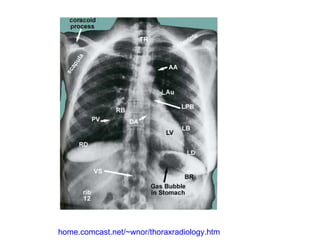

FR = 1ª costela M = manúbrio C = clavícula T = traquéia

home.comcast.net/~wnor/thoraxradiology.htm

FR = 1ªcostela M = manúbrio C = clavícula T = traquéia